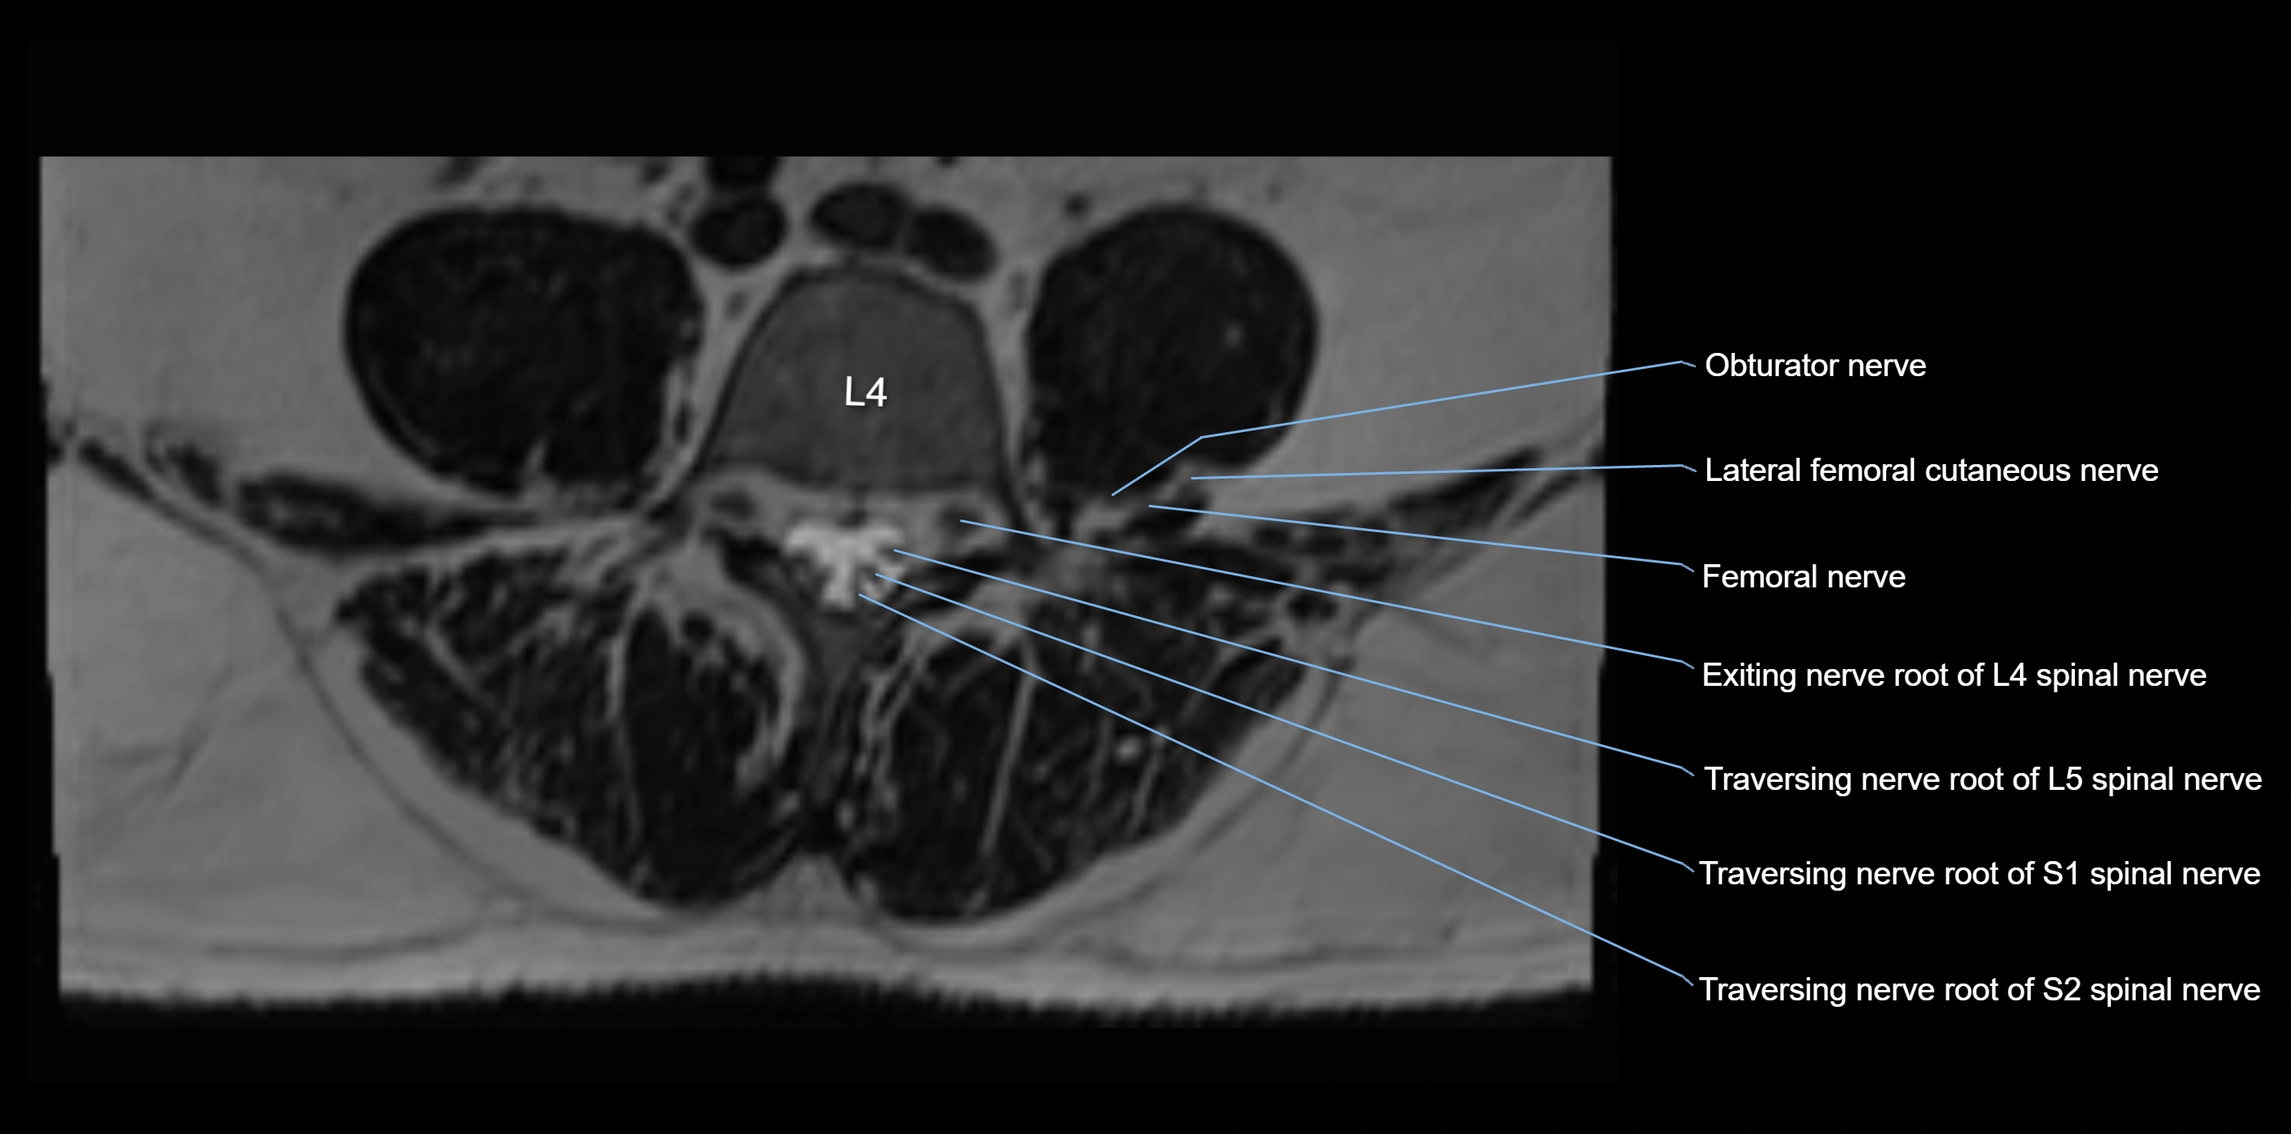

MRI Appearance

T1-weighted images:

• Nerve appears as a very thin low-to-intermediate signal intensity structure

• Surrounded by bright fat, aiding visualization

T2-weighted images:

• Nerve shows intermediate to mildly hyperintense signal compared to muscle

• Pathological involvement appears brighter

STIR (Short Tau Inversion Recovery):

• Normal nerve appears dark

• Inflamed or entrapped nerve appears bright hyperintense

T1 Fat-Sat Post-Contrast:

• Normal nerve enhances minimally

• Pathologic nerve (neuritis, entrapment, tumor infiltration) shows focal or diffuse enhancement

3D T2 SPACE / CISS:

• Nerve appears intermediate to mildly hyperintense compared to muscle

• Surrounded by bright fat or CSF, improving visualization

• Best sequence for mapping small pelvic nerves such as the anococcygeal

MRI image

image